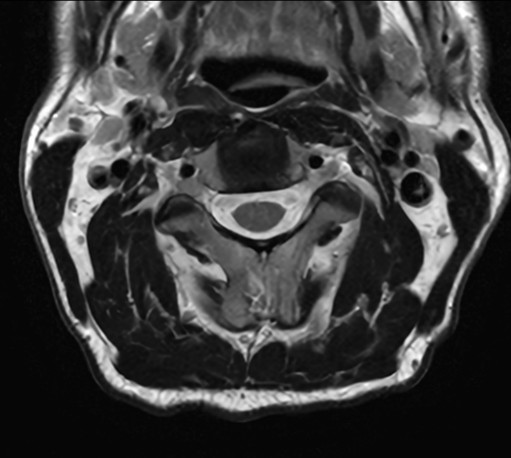

High quality Cervical Spine imaging with SmartSpeed Precise